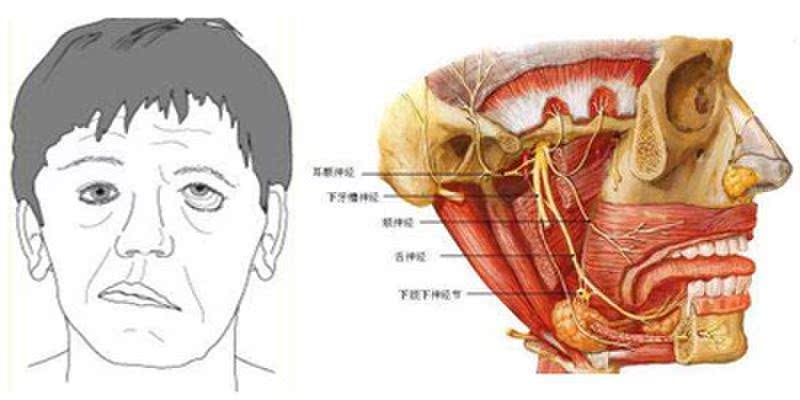

1、面神经炎:

面部受凉、吹风或感冒之后,可能会出现睡觉流口水的情况。